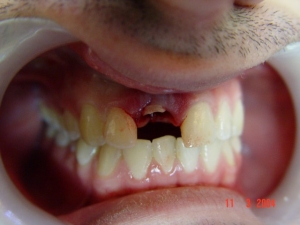

בחור צעיר, הגיע עם שן שבורה כתוצאה מתאונה. הוחלט לעקור את השן ולבצע שתל ושיקום

בוצעה עקירת השן